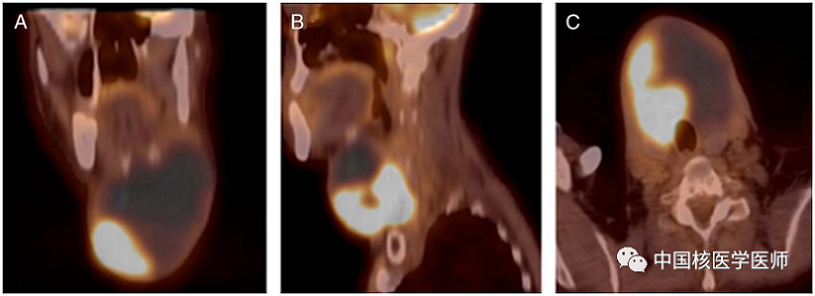

圖1.一63歲男性患者,有甲狀舌管囊腫病史,感冒樣癥狀3周后出現(xiàn)頸前腫塊迅速增大導(dǎo)致呼吸困難。圖A-C, 冠狀位、矢狀位、橫斷面顯示頸前區(qū)甲狀舌管囊腫的巨大囊性腫物。在CT上可以看到甲狀舌管囊腫右側(cè)不均質(zhì)軟組織腫塊。后來病理結(jié)果證實(shí)為鱗狀細(xì)胞癌。